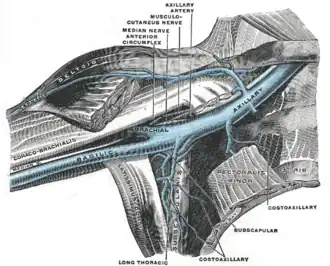

The port is usually inserted in the upper chest (known as a "chest port"), just below the clavicle or collar bone, with the catheter inserted into the jugular vein.

A port consists of a reservoir compartment (the portal) that has a silicone bubble for needle insertion (the septum), with an attached plastic tube (the catheter). The device is surgically inserted under the skin in the upper chest or in the arm and appears as a bump under the skin. It requires no special maintenance other than occasional flushing to keep clear. It is completely internal so swimming and bathing are not a problem. The catheter runs from the portal and is surgically inserted into a vein (usually the jugular vein or less optimally the subclavian vein). Ideally, the catheter terminates in the superior vena cava or the right atrium. This position allows infused agents to be spread throughout the body quickly and efficiently.

Right internal jugular vein (IJV) is frequently chosen as the site of access. A 19G puncture needle is used to obtain access to the vein under ultrasound guidance. The needle should be pointed away from the common carotid artery (CCA) as the CCA just lie medially to the IJV. If there is difficult puncture, micropuncture set can be used to puncuture the vein and later switch to a bigger access system. If bilateral IJVs are thrombosed, then right external jugular vein is chosen as the puncture site. The puncture site should not be the same side as the pathological site such as breast cancer site or an area that is chosen as the potential site for radiation therapy.[3]

After the entry site is punctured with ultrasound, a guidewire is inserted with the tip of the guidewire reaching the inferior vena cava. The proximal end of the guidewire is secured to prevent dislodgement. Then a chemoport pocket is created on the deltopectoral region at 2.5 cm below the level of clavicle by using a scalpel. Bupivacaine with adrenaline (0.25%) is used as local anesthetic to reduce the formation of haematoma and prolong the anesthetic effect. After the pocket is created, a trocar is used insert a silicone catheter from the pocket towards the internal jugular vein puncture site. A peel-away sheath is then inserted to facilitate the insertion of the silicone catheter into the cavoatrial junction. Silicone catether insertion should be done during breath hold at inspiration. The peel-away sheath should be pinched to prevent air embolism. The proximal end of the catheter is connected to the port within the skin pocket later after irrigation of the pocket with normal saline.[3]

The insertion site of the IJV is fixed between the two heads (sternal and clavicular heads) of the sternocleidomastoid. 2% lignocaine is to infiltrate the puncture site. Using a 24G needle attached to 5 cc syringe, the needle is advanced through the puncture site with its tip pointing towards the nipple of the same side. Once the backflow of venous blood is seen in the syringe, the puncture of the IJV is considered successful. Then a port needle is advanced through the pre-existing 24G needle and backflow of blood is confirmed by aspirating another syringe attached to the port needle. Then a guidewire is inserted through the port needle. The guidewire should not extend past the SA node of the right atrium as it can stimulate the heart arrhythmia. The port needle is then removed and the guidewire is fixed in place. The puncture is then widened by using 11-number knife and mosquito haemostat.[5]

The port access site is fixed at 5 cm below the midline of the clavicle and 9 to 10 cm lateral to the midline of the chest. Then, a 5 to 6 cm incision is made to create a subcutaneous tissue pouch for the placement of port access site. A tunnel is made from the port access site until adjacent to the internal jugular neck wound. A port catheter is passed through the tunnel where one end is attached to the chemport and another end is left hanging out near the IJV insertion site. The length of the hanging port catheter should be about 16 to 17 cm (or can be measured from the IJV insertion site until 2 cm below the sternal angle where the right atrium should begin). This portion of the port catheter should later be inserted through the IJV insertion site until it reaches the aortocaval junction. The IJV insertion is dilated using a plastic dilator. Peel-off sheath was then inserted over the guidewire. Blood is aspirated from the catheter to confirm the position. Then, the free-end of the port catheter is inserted through the peel-off sheath. After the tip of the port catheter is confirmed at the aortocaval junction, the peel-off sheath is taken-off by peeling away with two hands. While peeling off, the port catheter should remain in-situ. Stitches are only removed after 14 days post operation.[5]

Ports can be put in the upper chest or arm. The exact positioning itself is variable as it can be inserted to avoid visibility when wearing low cut shirts, and to avoid excess contact due to a backpack or bra strap. The most common placement is on the upper right portion of the chest, with the catheter itself looping through the right jugular vein, and down towards the patient's heart.